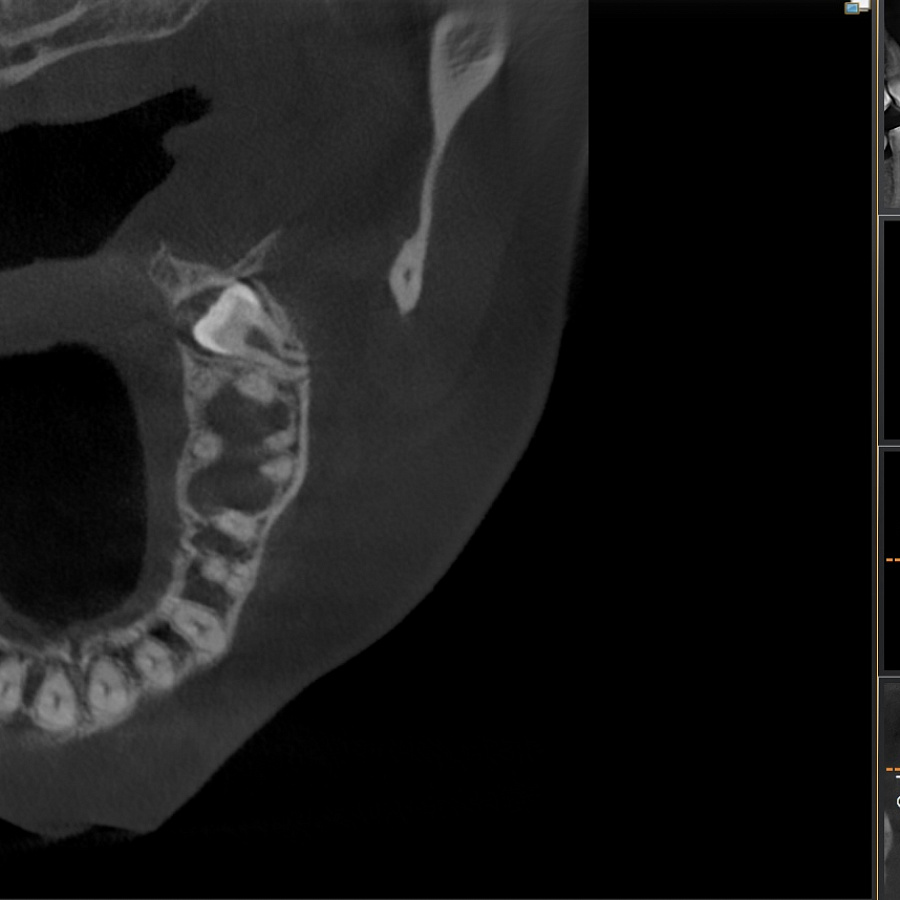

Зуб не прорезался, лежит горизонтально и направлен в сторону твёрдого нёба, мешает проведению ортодонтического лечения, выпрямлению зубных рядов. Около зуба проходит несколько важных анатомических структур, которые нельзя задеть, плюс зуб полностью погружён в костную ткань.

Зуб удалили за 1 час.